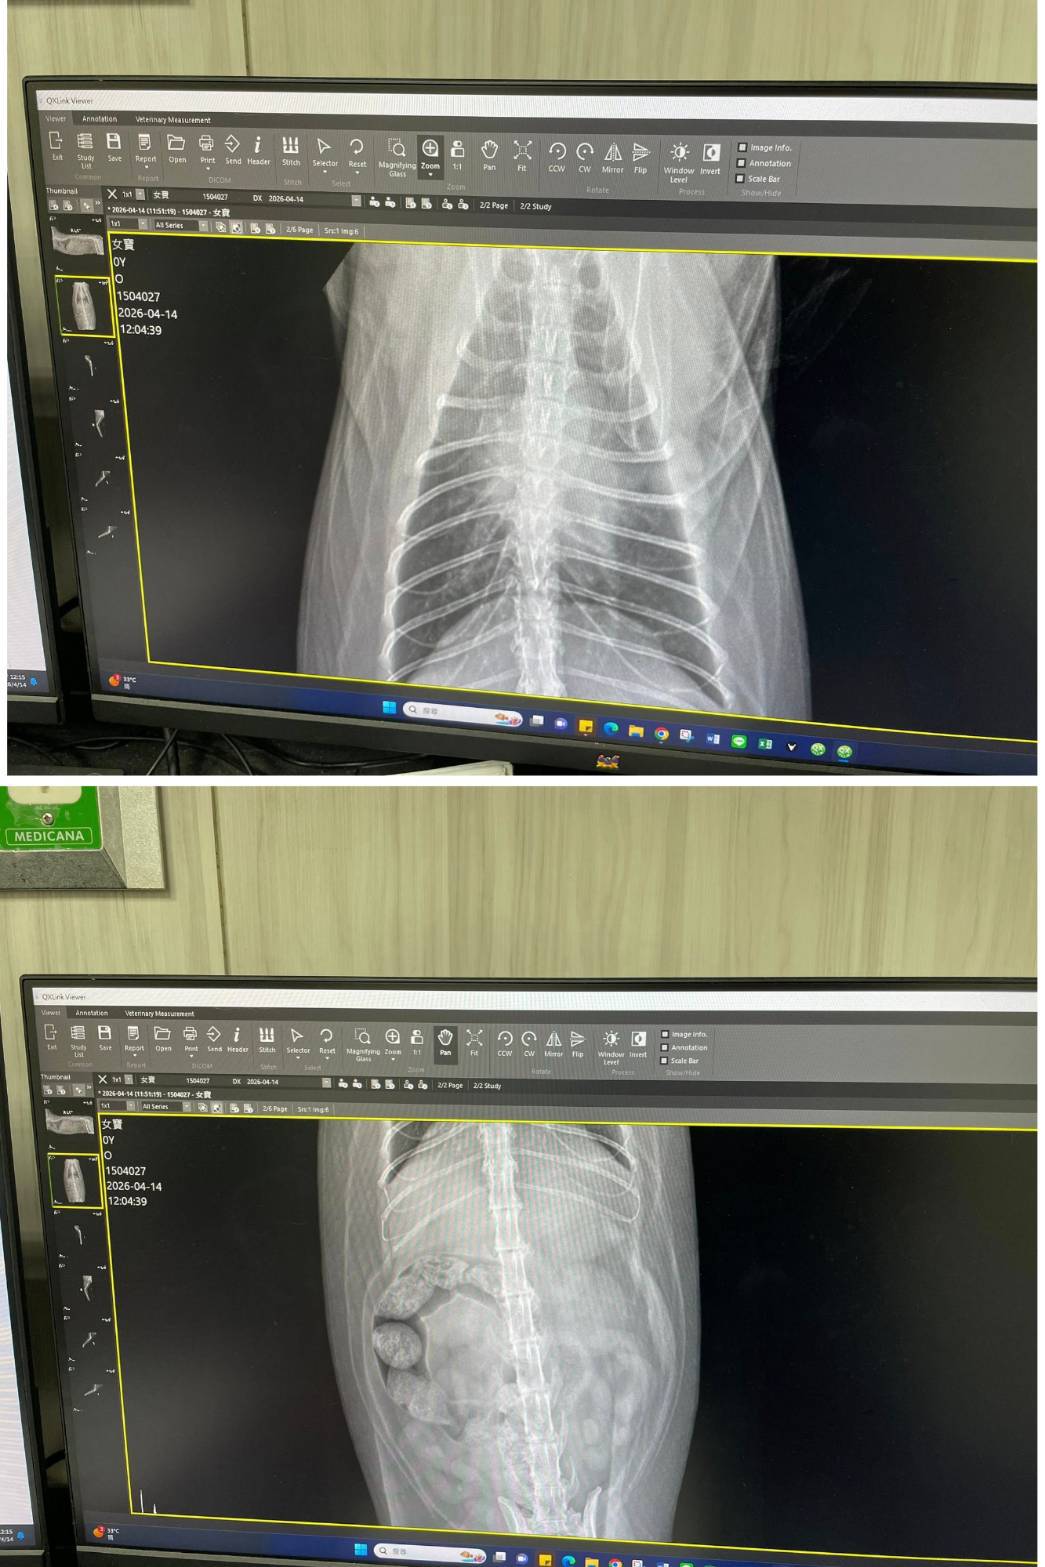

經X光檢查發現右前肢骨骼退化較嚴重,左邊也有一點骨骼退化;肺功能也是偏差;有牙周炎、牙齦萎縮所以齒根比較出來。X光有拍到兩顆東西,穿刺抹片檢查,淋巴細胞正常,淋巴結腫大。於醫院先點一錠除,並開立內用驅蟲藥,三個月後體外驅蟲需要再做一次。目前已於14日當日就醫後先行安置於協會幾日,因考量女寶年齡已大,汐止愛媽會帶回家中安置給女寶一個長久安穩的家。本筆醫助是女寶2026年4月14日於沐恩醫院看診的費用,包含血檢、X光、三合一、心臟快篩、皮膚抹片、一錠除滴劑及驅蟲藥。

右前肢比較嚴重左邊也有一點骨骼退化。

肺功能也是比較偏差。

X光有拍到兩顆東西,穿刺抹片檢查,淋巴細胞正常,淋巴結腫大,